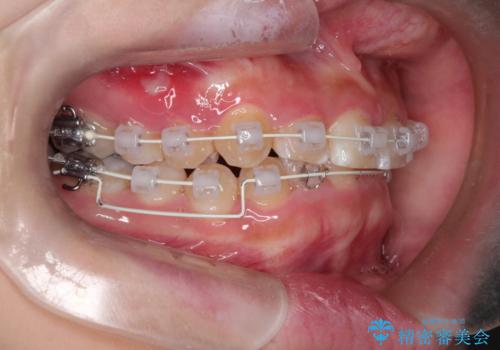

- 矯正装置

- 審美装置

- 前歯の凸凹と深い噛み合わせを主訴に来院されました。

下の前歯が見えないほどのディープバイト症例でした。

ワイヤー矯正にて下顎前歯の圧下と臼歯部の挺出を効率的に行うことができました。